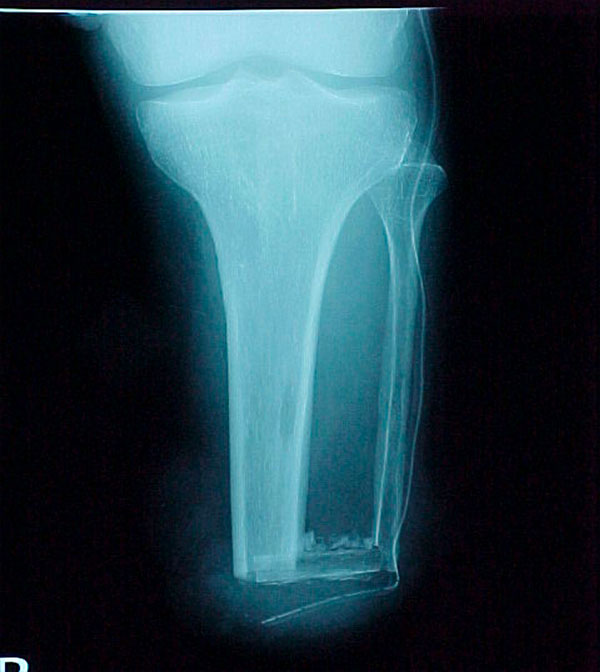

- Primary Objective RCT to evaluate the use of recombinant protein in patients at high risk for nonunion